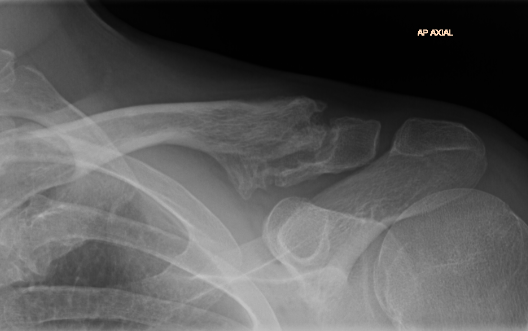

Neer Classification

Fracture lateral to the CC ligaments Non displaced

Fracture medial to the CC ligaments CCL ligaments attached to lateral fragment Medial fragment displaced superiorly |

Between conoid and trapezoid Conoid disrupted Trapezoid remains attached to the lateral fragment |

Lateral to CC ligaments Intra-articular extension Stable |

Periosteal sleeve disruption Pediatric Medial fragment displaced |

Comminuted Type II Medial fragment displaced |

Type I

Type II

Type V